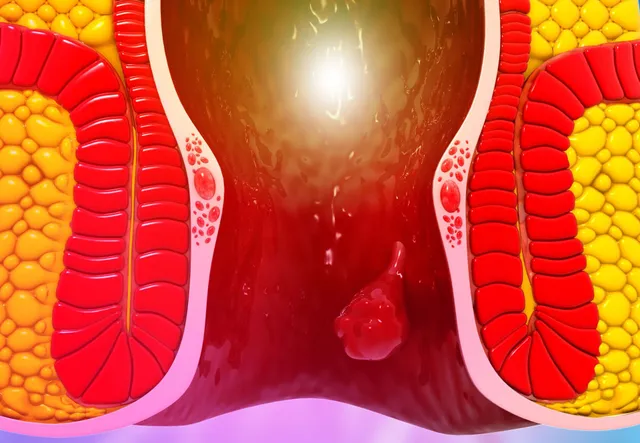

Seeing blood during passing stool can be frightening. While many people ignore it or delay talking to a doctor due to embarrassment, rectal bleeding should never be ignored.